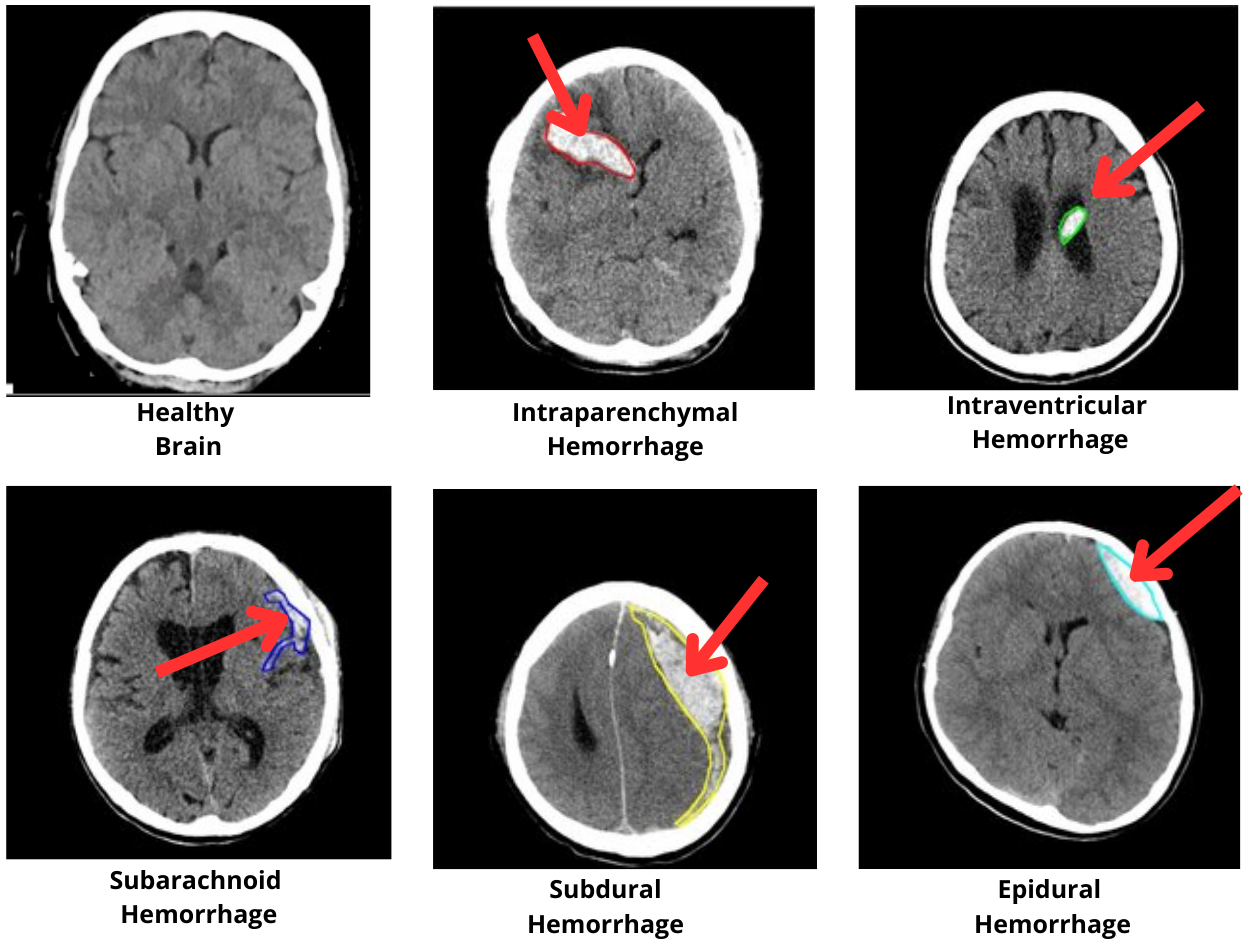

We evaluate our approach using the RSNA Intracranial Hemorrhage Detection Challenge (IHDC) dataset [34], which consists of 674,258 brain CT images from 19,530 patients, annotated by 60 radiologists over 30 epochs. Each image is labeled as either ”normal” or as presenting one of the five types of intracranial hemorrhage. Figure 3 shows annotated brain CT images from the RSNA dataset, illustrating the diversity of hemorrhage types (epidural, subdural, subarachnoid, intraparenchymal, and intraventricular) available for training AI-based diagnostic models. This dataset is essential for developing AI models capable of automatically detecting and classifying hemorrhages in brain CT images. The scans are accompanied by metadata such as the patient’s age, allowing for a more comprehensive contextual analysis.

Figure 3: Examples of brain CT images showing different types of intracranial hemorrhages: epidural, subdural, subarachnoid, intraparenchymal, and intraventricular hemorrhages from the RSNA Intracranial Hemorrhage Detection Dataset.